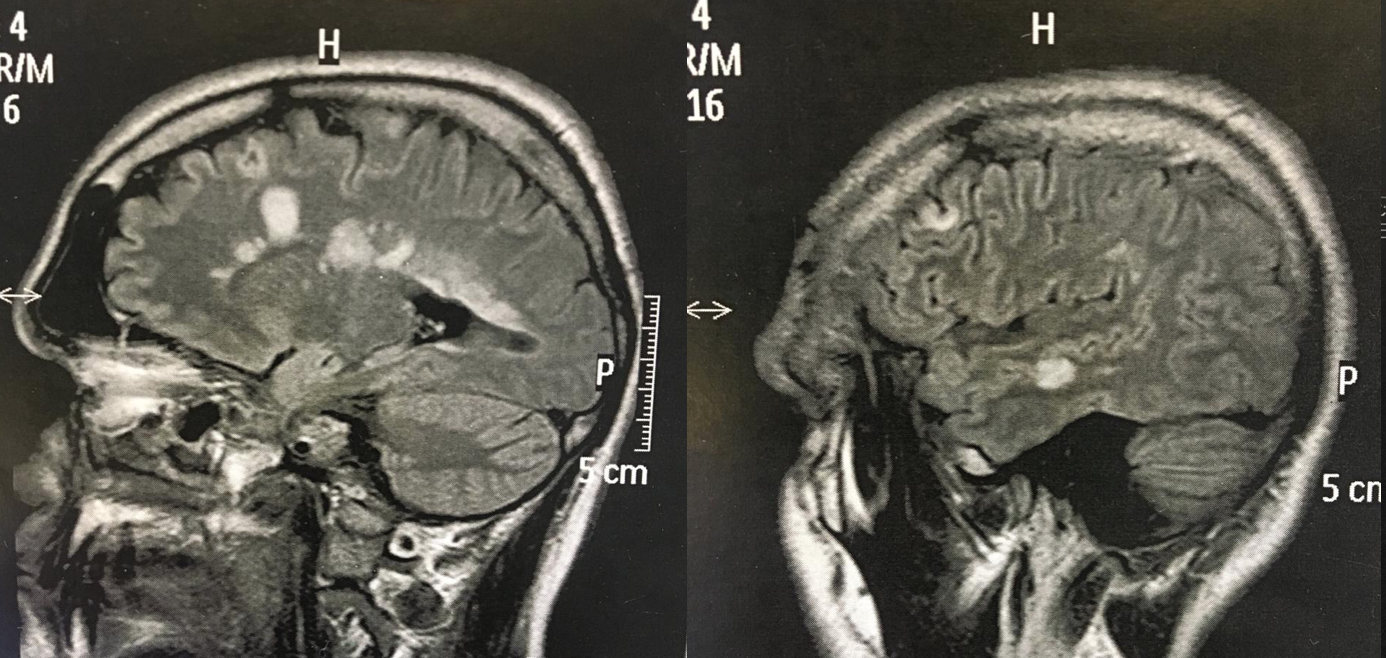

Exames de Imagem

incluir as imagens e as caracteristicas de em